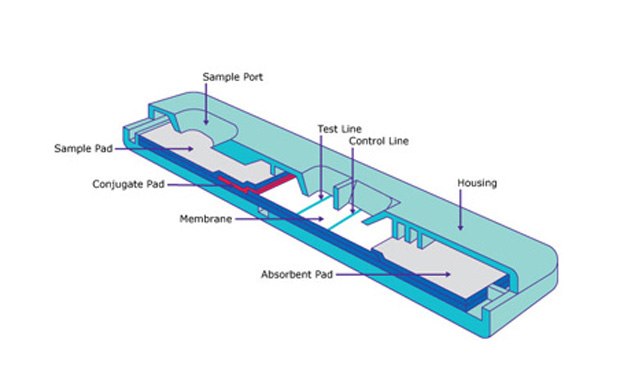

Lateral Flow Membranes

Discover critical membrane materials for your IVD lateral flow immunoassay development including Hi-Flow™ lateral flow membrane cards and SureWick® pad materials.